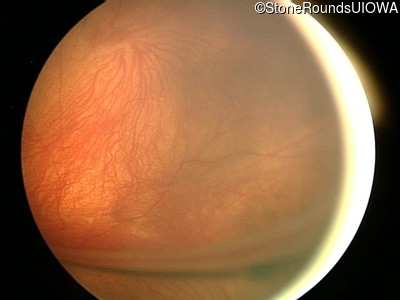

Fundus Photography - Left - 20/250

Exemplar